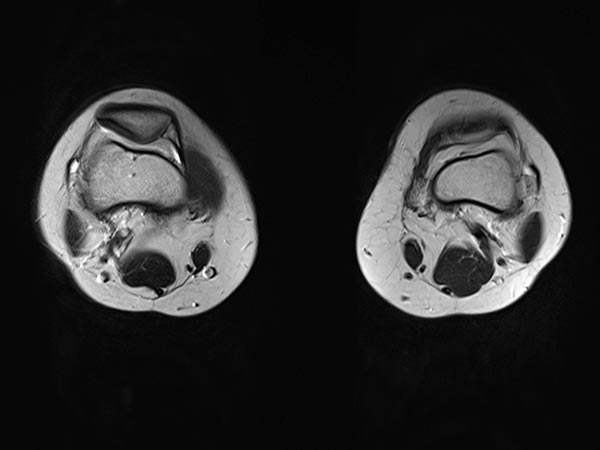

The completely occluded venous malformation, which in this case had contained multiple arteriovenous fistulas, was successfully resected after successful embolization and sclerotherapy with complete occlusion. Axial T2-weighted MRI demonstrates the completeness of the resection without a remaining lesion.

The completely occluded venous malformation was successfully resected after successful embolization and sclerotherapy following complete occlusion. The patient has thus far been asymptomatic (3 years, 4 months).